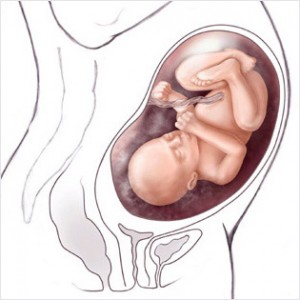

Bu haftadan itibaren artık bebek rahim içerisinde oldukça fazla yer kaplar ve bu yüzden ona hareket edecek fazla alan kalmaz. Eğer bebeğinizin hareketlerinde azalma his ederseniz endişe etmeyin, hareketlerin azalması bu yüzdendir.

Bebeğin Boyutu: 43.7 cm, 1.9 kg